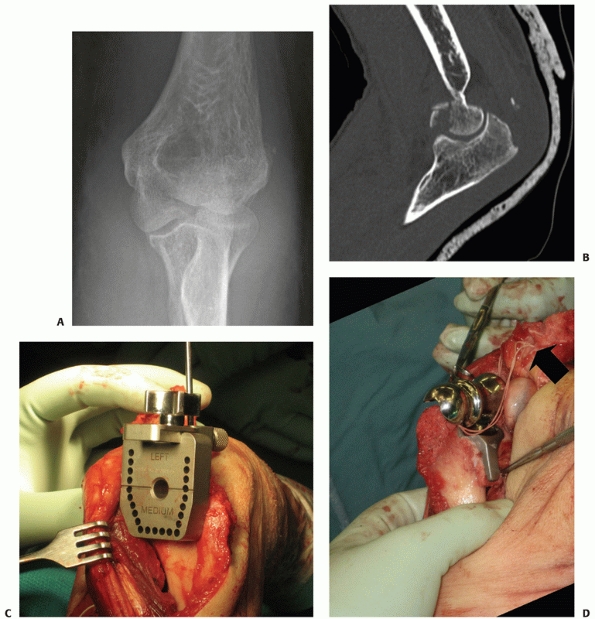

FIGURE 33-21 An AP injury radiograph (A)

demonstrating a displaced intra-articular distal humerus fracture in association with an ipsilateral humeral shaft fracture. The fractures were exposed via a paratricipital approach extended proximally into a Gerwin et al.53 approach. The patient’s distal humerus fracture was fixated with orthogonal 3.5-mm dynamic compression plates (B,C) that were intra-operatively contoured. This technique has been popularized by the AO group and involves the placement of plates at 90-degree angles to each other. Usually, the lateral plate is placed as distal as possible along the posterior aspect of the lateral column. The medial plate is placed over the medial supracondylar ridge and curved around the medial epicondyle. |